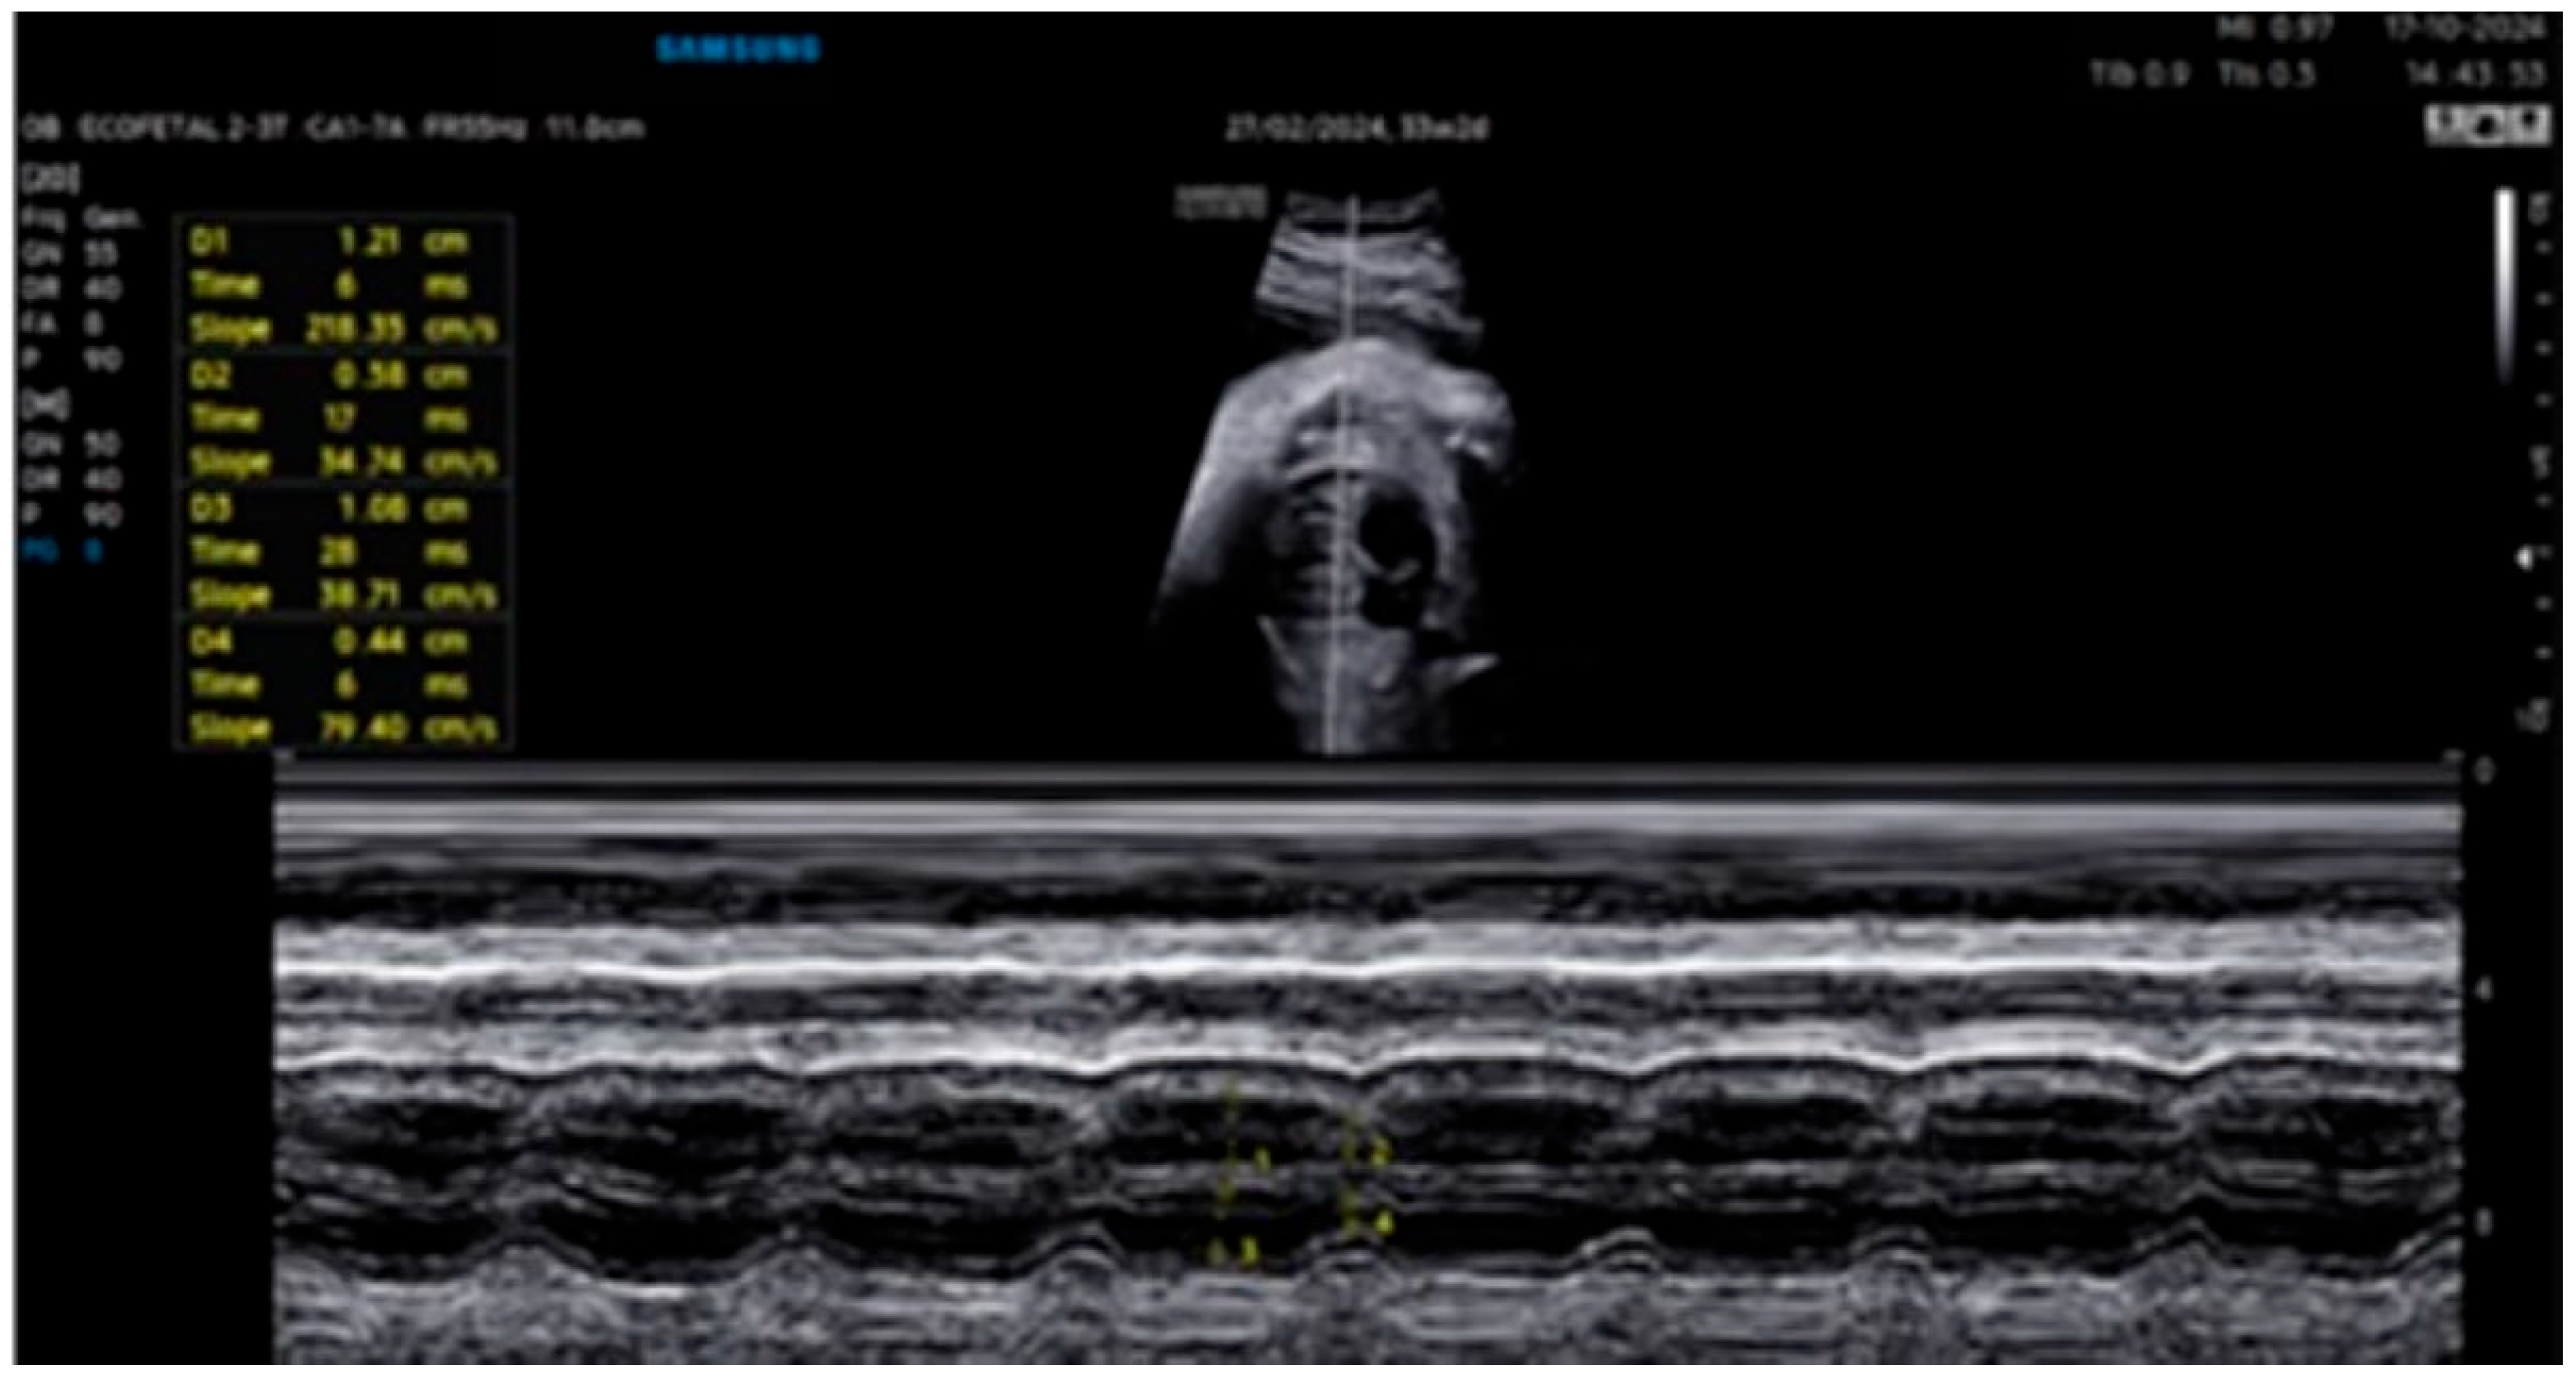

| 26 + 0 | Start of dexamethasone 4 mg/day | 60 | SF increased from 34% to 47%, but qualitative contractility decreased | Mild edema; no beta- agonists used |

| 28 + 0 | First IVIG cycle (65 g total) | 75 | SF increased to 52%; mild improvement in contractility | Initiated due to signs of fibroelastosis |

| 31 + 2 | Post-IVIG peak response | 70 | SF: 59% (LV), 52% (RV); marked biventricular improvement | Aortic isthmus 3 mm (Z-score –1.65) |